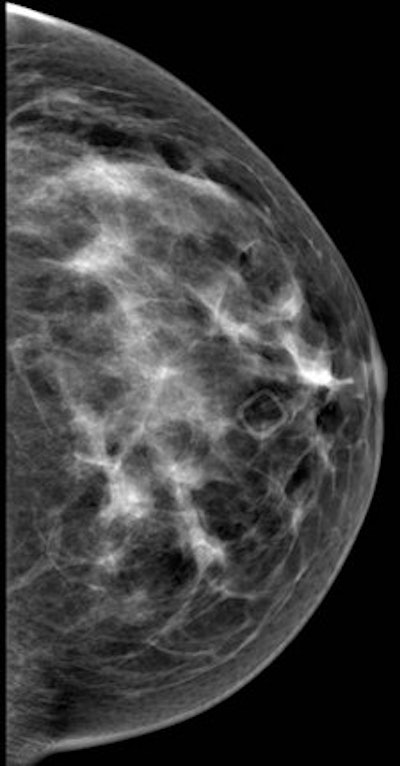

Left mediolateral oblique (left image) and left cranial-caudal (right image) unilateral diagnostic mammogram for a 42-year-old women presenting with new palpable lump in the left upper central breast with no suspicious finding on mammogram. All images courtesy of Dr. Rola Shaheen, originally appearing in the 2014 show Issue of Arab Health magazine.